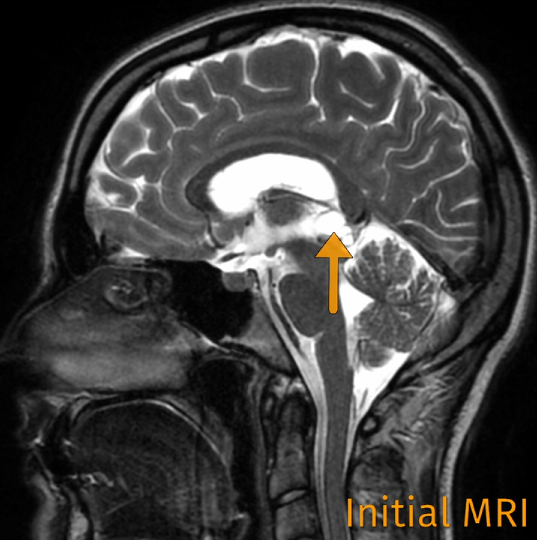

她的腦子里,松果體區(qū)長了一個囊腫。

“大概率是沒什么問題的,但也可能長大,導(dǎo)致梗阻性腦積水,帶來一系列癥狀。”

不好的是,松果體這個位置十分重要。

它藏在松果體區(qū)位于大腦深部顱腔中心,是調(diào)節(jié)人體晝夜節(jié)律的中線軸外神經(jīng)內(nèi)分泌結(jié)構(gòu)。不僅如此,松果體區(qū)還與我們的情緒、免疫力乃至生殖功能息息相關(guān)。

體積巨大的松果體囊腫可阻塞中腦導(dǎo)水管,引起梗阻性腦積水及其相應(yīng)臨床表現(xiàn),需手術(shù)切除。

頭越來越疼,可最要命的是,不可怕的囊腫肉眼可見長大了。

隨后改換0°及45°神經(jīng)內(nèi)鏡復(fù)查:神經(jīng)血管、松果體均保留完好。術(shù)后第1天MRI示囊腫已全切除,中腦導(dǎo)水管通暢。珍術(shù)后第5天順利出院。